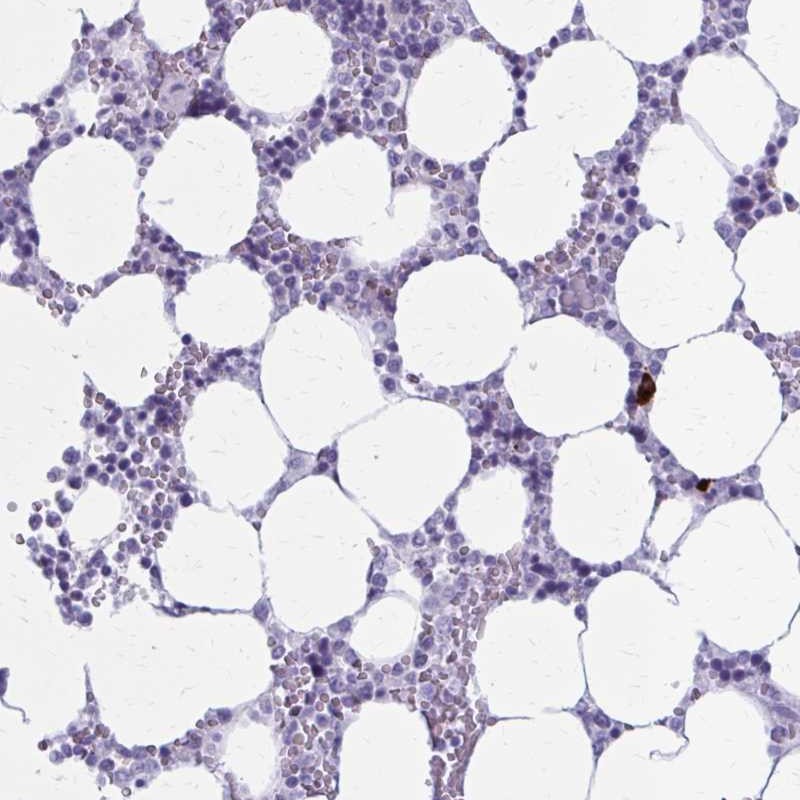

Immunohistochemical staining of human bone marrow shows strong cytoplasmic positivity in a subset of hematopoietic cells.